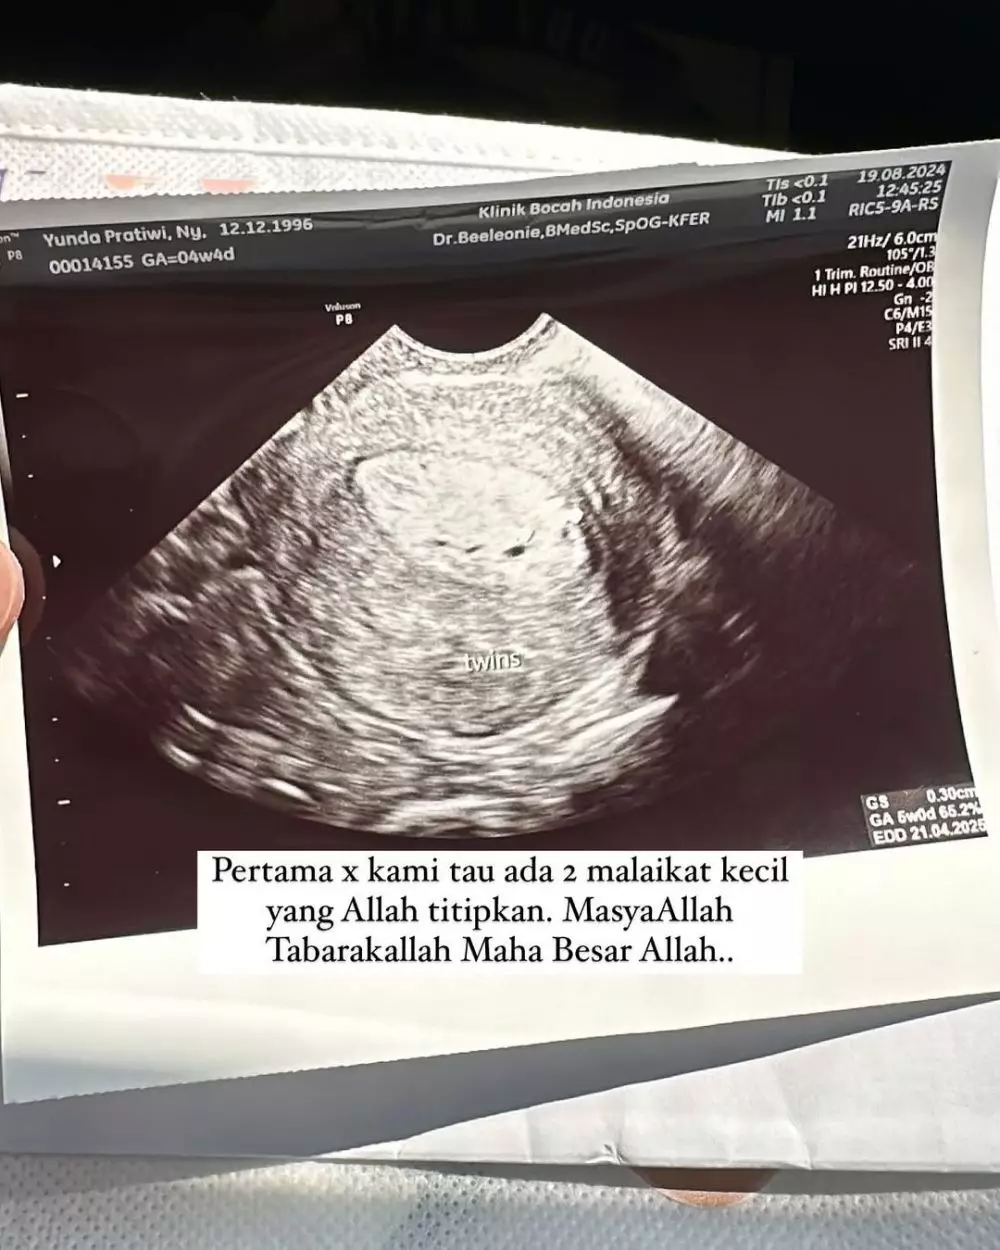

Berkat berbagai usaha dan doa dari berbagai pihak terutama orang tua, kini perjuangan Dennis Lim dan istri membuahkan hasil. Sang istri kini sedang mengandung buah hati kembar, setelah penantian lima tahun. Bahkan dalam satu slide terlihat, bahwa kandungan Yunanda Faisyah kini sudah jalan 5 bulan.

"Alhamdulillah atas pertolongan Allah bisa ngasih berita bahagia untuk atok & neneknya," tulis Yunanda Faisyah.